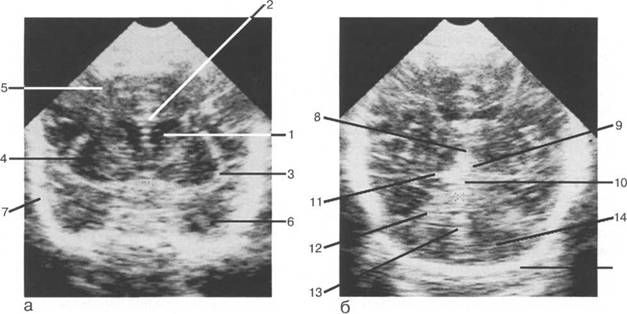

Задняя череп 13513u2010n 85;ая ямка представляет собой часть основания череп 13513u2010n 72;, ограниченную централь

Следует отметить, что в настоящее время оптимальным методом исследования структур задней череп 13513u2010n 85;ой ямки является МРТ, которая, в отличие от КТ, лишена артефактов от кост

Мозжечок заполняет практически весь объем задней череп 13513u2010n 85;ой ямки. Его поперечный раз

Следует остановиться на анатомии подпаутинных пространств задней череп 13513u2010n 85;ой ямки IV 20 мм. Между основанием череп 13513u2010n 72; и нижней поверхностью мозга от большого затылочного отверстия вдоль ската и спинки турецкого седла простирается задняя базальная цистерна. В зави IV